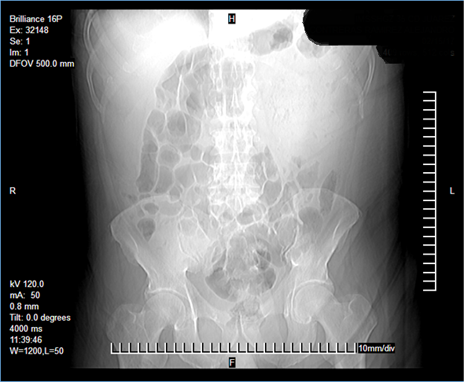

Laboratorios a su ingreso: hemoglobina 9,3 g/dL, hematocrito 29,6 %, plaquetas 574 x 109/L y albumina 1,6 g/dL, resto dentro de parámetros normales. Se realizó una tomografía abdominal que reportó un tumor dependiente del colon transverso con invasión a pared abdominal y formación de absceso (Figura 1, 2 y 3). Con el paciente en estado séptico, se decide el drenaje y la exploración quirúrgica previa estabilización.

Figura 1. Imagen que muestra el aumento de la densidad del cuadrante superior izquierdo, distensión y edema interesa en el resto de los cuadrantes. Fuente: archivo electrónico del HGZ No. 35 (IMSS).